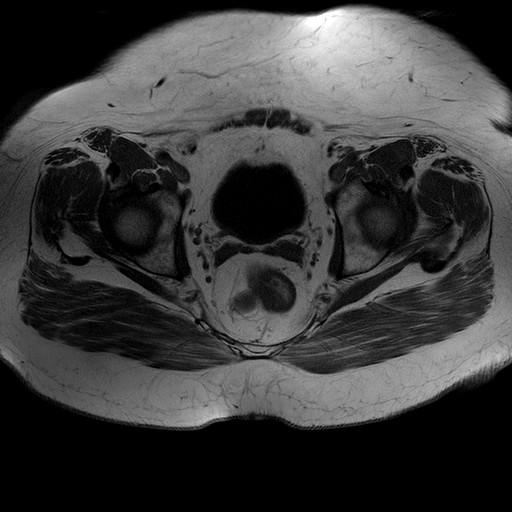

Esami: RMN BACINO

Evidenti e simmetriche alterazioni osteofitosiche in regione coxo femorale con riduzione delle rime articolari. Degenerazione completa del cercine glenoideo. Non attuali segni di versamento articolare. Non segni di edema osseo che escludono attuale algodistrofia od osteonecrosi. Lieve e simmetrica riduzione del trofismo della muscolatura glutea.